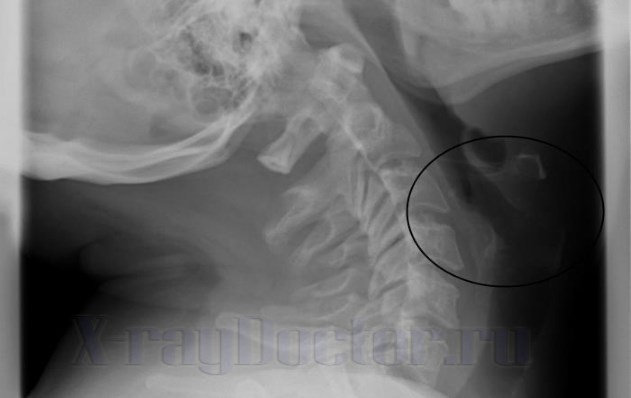

На рентгенограмме в боковой проекции можно увидеть полосы просветления, которые указывают на сужения просвета трахеи и глотки. Передняя стенка органа начинается от корня языка. Данная анатомическая структура относится к группе мягких тканей, через которые рентгеновские лучи проходят насквозь.

- сужение просвета глотки;

- аденоиды, заполняющие просвет глотки на ½, — 2-я степень болезни;

- аденоиды, заполняющие просвет глотки на 2/3, – 3-я степень.